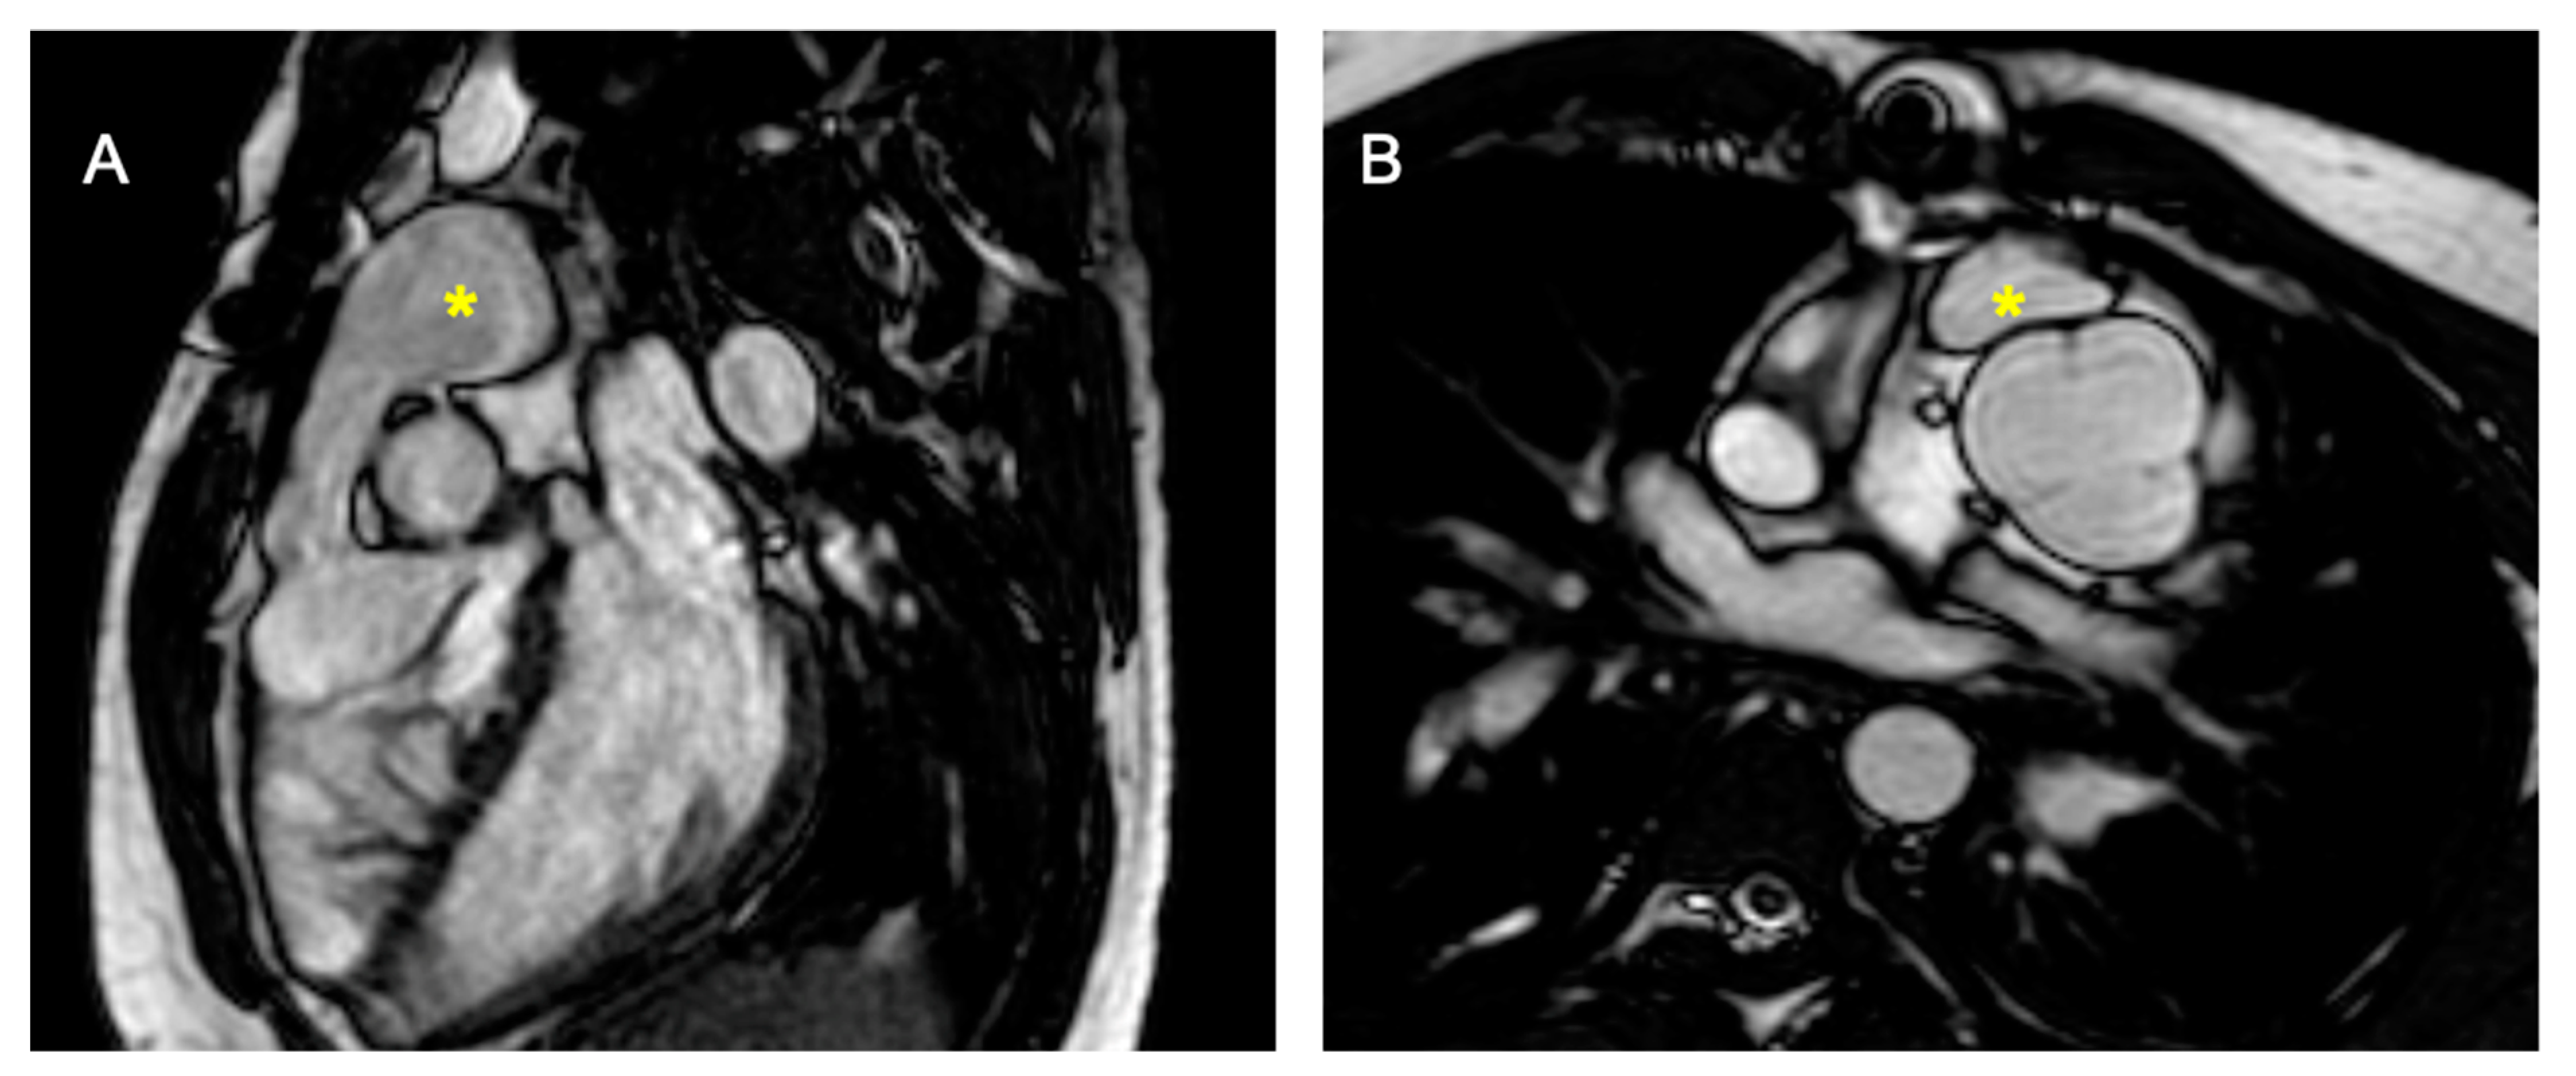

2.2.1. Dextro-Transposition of the Great Arteries (D-TGA)

Atrial Switch Operation and the Role of CMR Imaging

Arterial Switch Operation and the Role of CMR Imaging